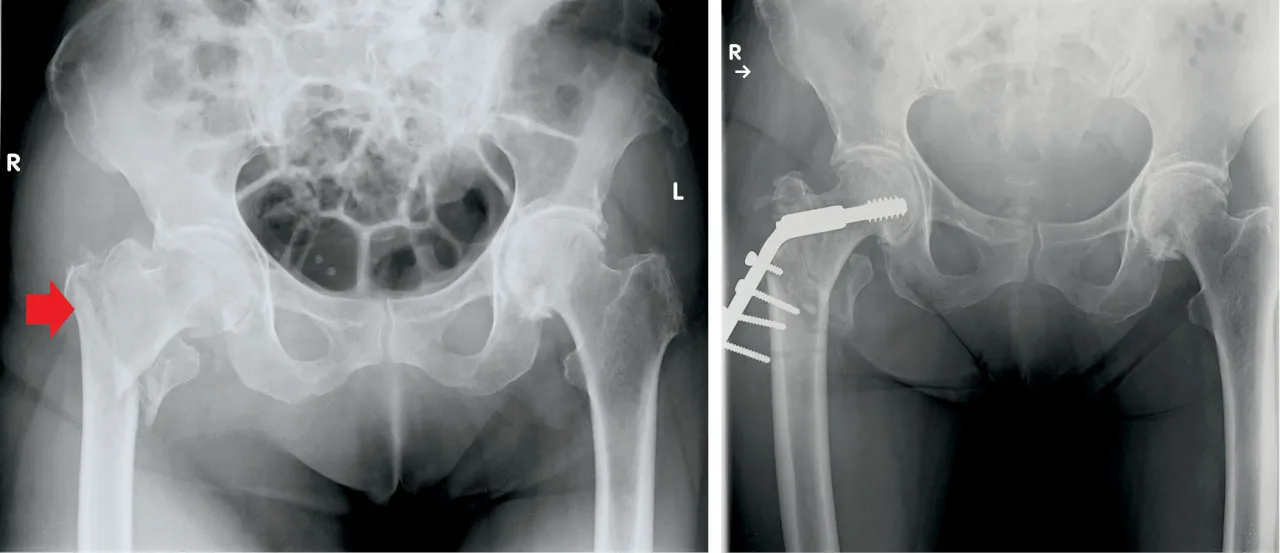

Rodzaj złamania

Złamanie kości udowej może dotyczyć różnych jej części, co wpływa na czas zrastania. Złamania trzonu kości udowej zazwyczaj goją się szybciej niż złamania szyjki. Wynika to z lepszego ukrwienia trzonu kości. Złamanie szyjki kości udowej często wymaga dłuższego okresu rekonwalescencji, szczególnie u osób starszych, ze względu na gorsze ukrwienie tej okolicy.

Metoda leczenia

Leczenie złamania kości udowej może być operacyjne lub zachowawcze, co wpływa na czas gojenia. Operacja, polegająca na stabilizacji złamania za pomocą implantów, często przyspiesza proces gojenia. Leczenie zachowawcze, stosowane rzadziej, może wydłużyć czas powrotu do sprawności, ale jest konieczne w niektórych przypadkach.